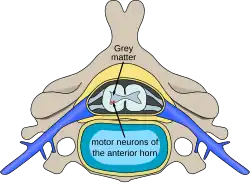

| Location of neurons affected by spinal muscular atrophy in the spinal cord | |

In individuals affected by SMA, the SMN1 gene is mutated in such a way that it is unable to correctly code the SMN protein – due to either a deletion[22] occurring at exon 7[23] or to other point mutations (frequently resulting in the functional conversion of the SMN1 sequence into SMN2). Almost all people, however, have at least one functional copy of the SMN2 gene (with most having 2–4 of them), which still codes 10–20% of the usual level of the SMN protein, allowing some neurons to survive. In the long run, however, the reduced availability of the SMN protein results in the gradual death of motor neuron cells in the anterior horn of spinal cord and the brain. Skeletal muscles, which all depend on these motor neurons for neural input, now have decreased innervation (also called denervation), and therefore have decreased input from the central nervous system (CNS). Decreased impulse transmission through the motor neurons leads to decreased contractile activity of the denervated muscle. Consequently, denervated muscles undergo progressive atrophy (waste away).